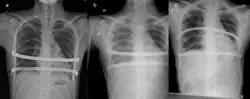

![]() X-Ray of a 15-year-old male after undergoing the procedure | |

The Nuss procedure is a minimally invasive procedure, invented in 1987 by Dr. Donald Nuss and his colleagues, Dr. Daniel Croitoru and Dr. Robert Kelly, for treating pectus excavatum.[1][2][3] He developed it at Children's Hospital of The King's Daughters, in Norfolk, Virginia. The operation typically takes approximately two hours.[4]: 1277 [5]

Through two small incisions in the side of the chest, an introducer is pushed along posterior to the sternum and ribs, and anterior to the heart and lungs. Then a concave stainless steel bar is slipped under the sternum, through the incisions in the side of the chest. A third, smaller incision is made to insert a thoracoscope (small camera) used to help guide the bar. Taller patients, older patients, or patients requiring extensive correction may receive two or more bars. All bars may be placed through two incisions or additional incisions may be made. The bar is then flipped, and the sternum pops out. To support the bar and keep it in place, a metal plate called a stabilizer may be inserted with the bar on one side of the torso. PDS sutures may also be used in addition to the stabilizer. The stabilizer fits around the bar and into the ribcage. The bar and stabilizer are secured with sutures that dissolve in about six months.